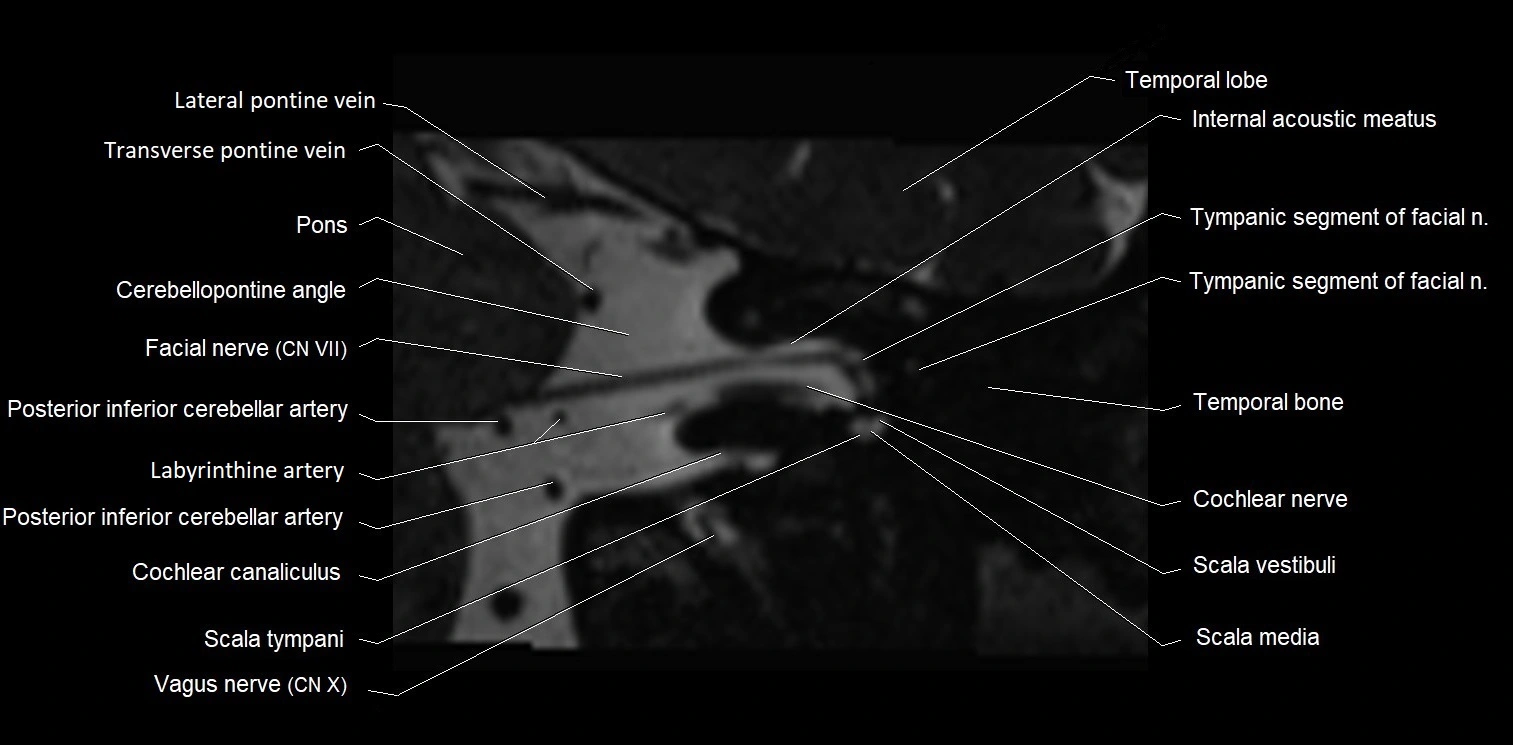

MRI Appearance

• The abducens nerve is a small, thin, linear structure

• Best visualized on high-resolution T2-weighted 3D MRI sequences (e.g., FIESTA or CISS)

• Seen as a hypointense (dark) line running from the brainstem at the pontomedullary junction, traversing the prepontine cistern, and entering Dorello’s canal under the petrosphenoidal ligament, then into the cavernous sinus, and finally the orbit

• May be challenging to visualize in standard MRI due to its small size

• Pathology may be inferred by absence, displacement, or enhancement of the nerve